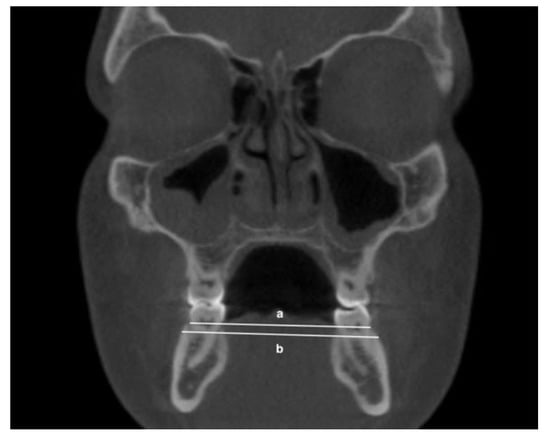

- Mandibular inter-buccal bone widths: from the right to the left points at the level of alveolar crest and furcation (Figure 3)